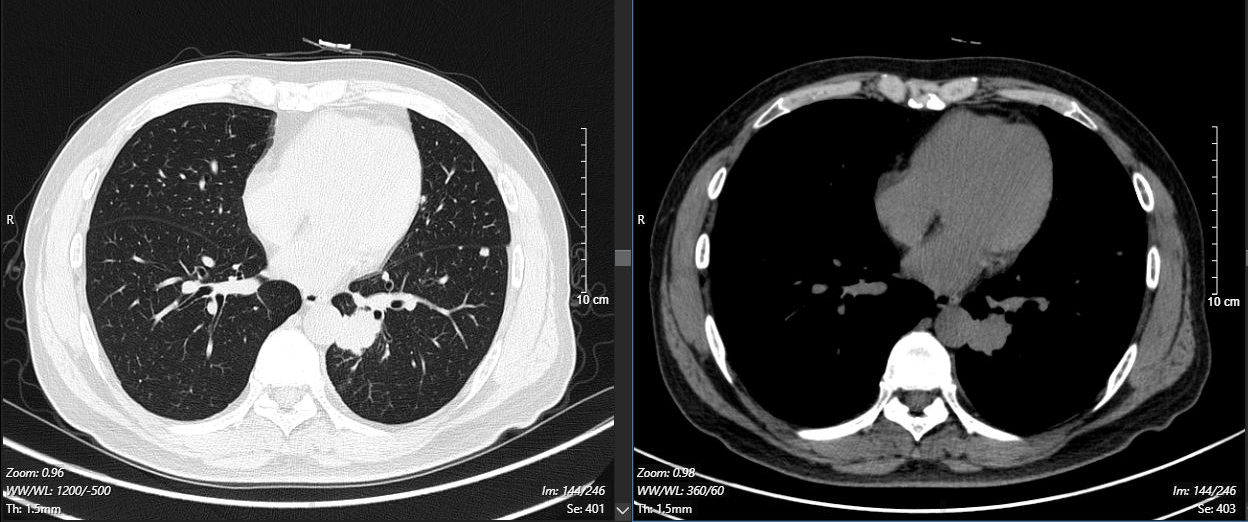

2024-11-26 胸部CT检查示:

2024-11-26 PET-CT进一步评估:左肺下叶背段近肺门处类圆形分叶状肿块(约32*28mm),FDG代谢异常增高;纵隔内4L组、左下肺门处、左侧膈肌脚内侧见稍大淋巴结FDG代谢增高,左肺内及胸膜下散在多发结节影,FDG代谢不同程度增高,考虑左肺下叶肺癌伴左肺及胸膜多发转移、多发淋巴结转移。